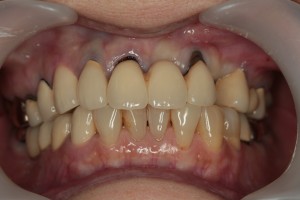

症例⑤

上左右の奥歯を失ってしまったため、保険の入れ歯を入れたが、違和感が強く、しっかり噛むことができないため、インプラントを併用した入れ歯を作ることで違和感なく、しっかり噛むことができるようになった。 また通常の入れ歯は、はずれないようにするため金属のバネを歯に引っ掛けるため見た目も悪いが、インプラントによって固定されているためバネもなく、見た目も非常に良いものとなっている。

術前